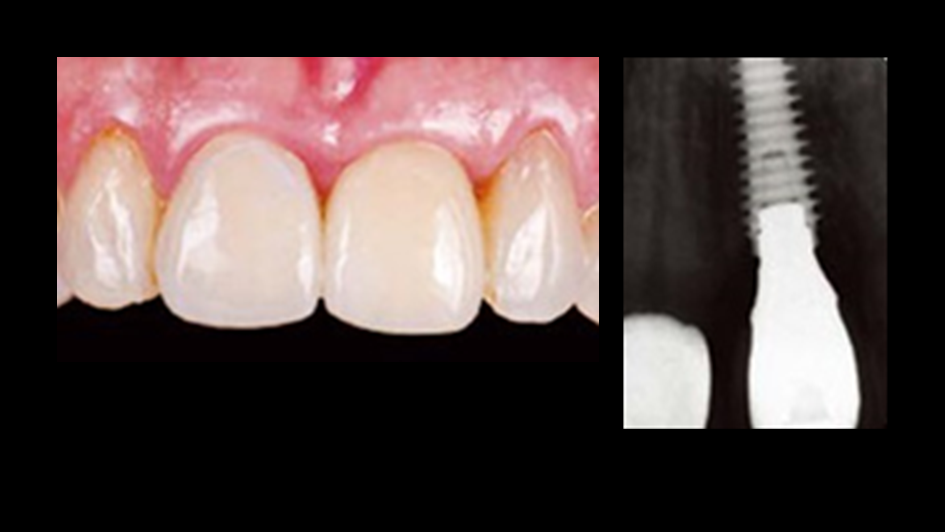

“AnyRidge with Root Membrane Technique shows

comparable long-term success rates to

conventional immediate implants. ”

Clinical case: Replacement of fractured central incisor (#11) with immediate implant

& Root Membrane Technique

- Courtesy of Dr. Miltiadis Mitsias, Greece -

AnyRidge, Root Membrane Technique, retrospective study, long-term study, immediate implants, bone resorption, bone preservation, Dr. Miltiadis Mitsias,survival, success, maxillary anterior, single replacement

AnyRidge implant system, Root Membrane kit

The Root Membrane Technique: A retrospective clinical study with up to 10 years of follow-up./Implant Dent. 2018 Oct;27(5):564-574

https://www.ncbi.nlm.nih.gov/pubmed/30161062